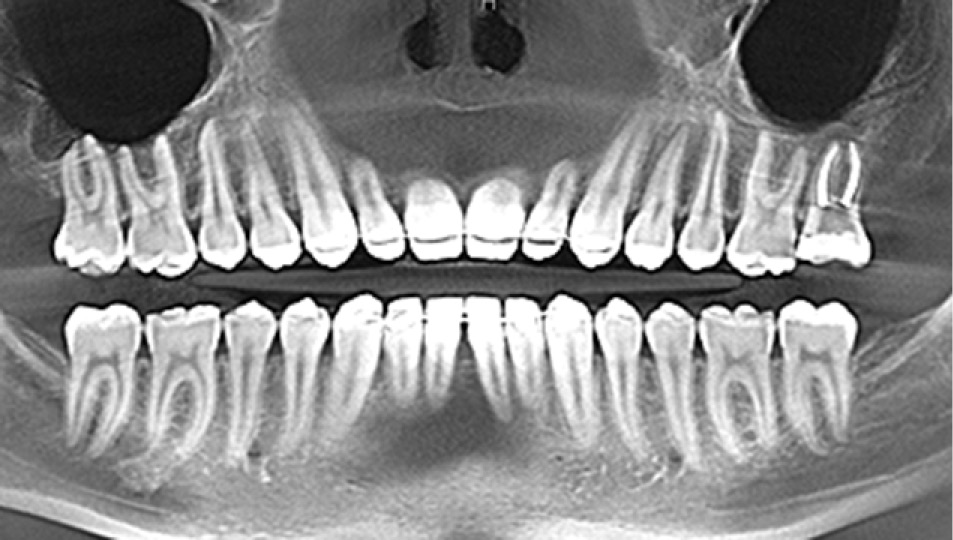

Пациент С., 28 лет. Зуб 2.7 после эндодонтического лечения. Данные объективного исследования: открывание рта — в полном объёме. Прикус ортогнатический. Зуб 2.7: временная реставрация, корневые каналы обтурированы до физиологической верхушки (рис. 11).

Рис. 11. Зуб 2.7 после эндодонтического лечения по поводу осложнённого кариеса.

Fig. 11. Tooth 2.7 after endodontic treatment for complicated caries.